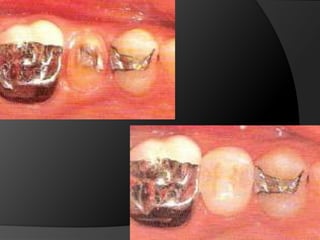

INLAY DE METAL: Restauraciones pequeñas o medianas con pocos requerimientos estéticos. El material de elección	 es el oro.  (OP – OMD)INLAY DE CERÁMICA: Estética y Adhesión a la estructura dentaria. (OP – OMD)

ONLAY MOD: Lesiones  moderadamente grandes en premolares y molares con superficie s vestibularesintactas. 	Si hay un reborde marginal comprometido es necesario el recubrimiento cuspídeo. No debe ser utilizado como retenedor de P.P.F.

INLAY DE METAL:Restauraciones pequeñas o medianas con pocos requerimientos estéticos. El material de elección es el oro. (OP – OMD)INLAY DE CERÁMICA: Estética y Adhesión a la estructura dentaria. (OP – OMD)